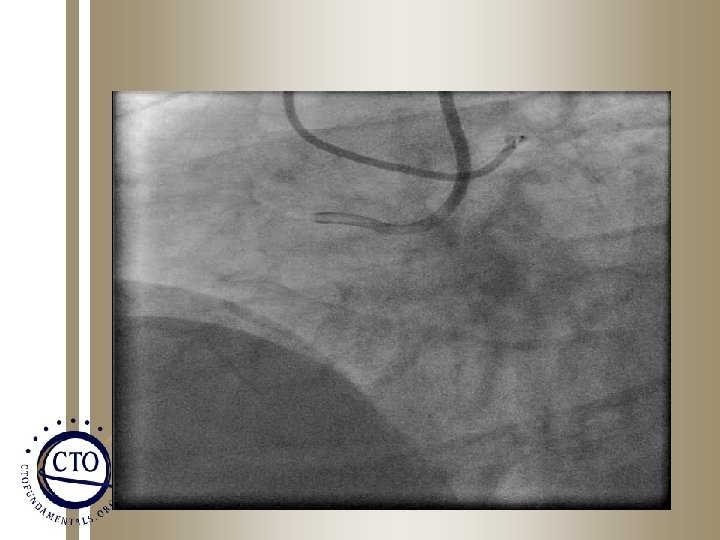

RCA CTO Primary Dissection Reentry Strategy